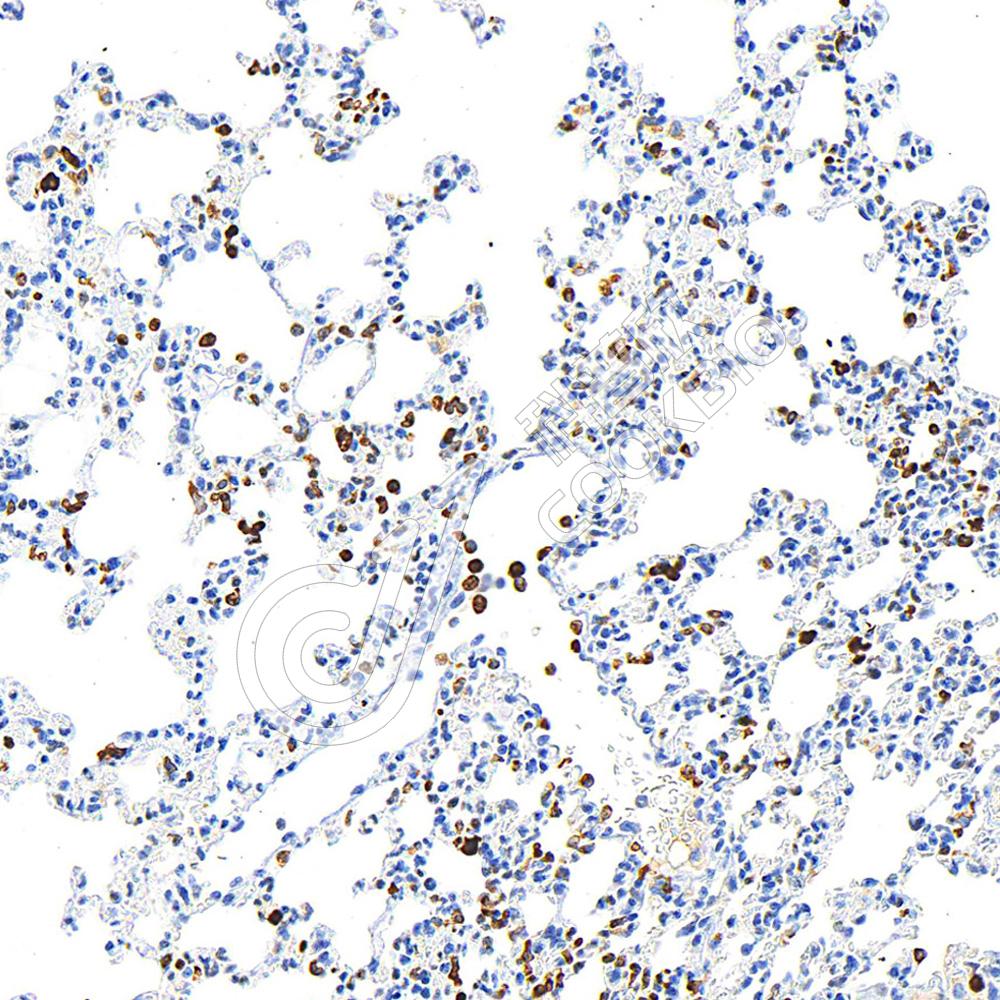

IHC检测Heme Oxygenase 1蛋白(货号 K545312).

样品: 小鼠lps(24h)肺诱导炎症模型, 4%多聚甲醛 (货号KSG1101) 固定12-24小时.

抗原修复: 柠檬酸抗原修复液(干粉, pH 6.0) (KSG1201), 高压锅均匀喷气计时2分钟.

—抗: 1: 800稀释, 4℃ 孵育过夜.

二抗: S-vision免疫组化多聚二抗(山羊抗小鼠), 即用型(货号KB3903), 室温孵育20分钟.